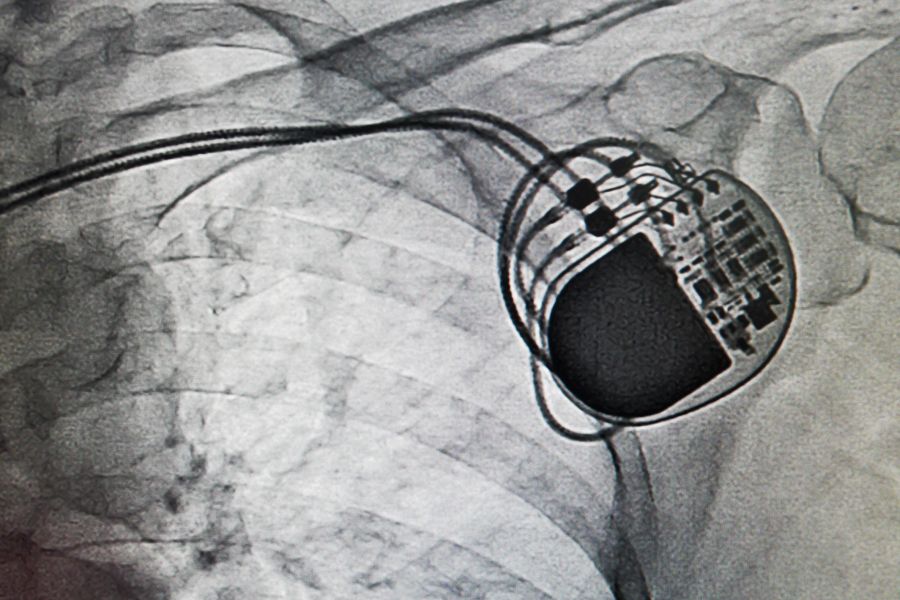

Stymulator serca, lub inaczej rozrusznik serca, jest urządzeniem elektrycznym, którego zadaniem jest elektryczne pobudzanie rytmu pracy serca. By mógł spełniać swoje zadanie, rozrusznik serca wszczepia się do ciała pacjenta. Jest to niewielkie urządzenie – wielkością przypomina kopertę zegarka, waży nie więcej niż 30 gramów i składa się ze stymulatora wyposażonego w baterię oraz elektrod, które wprowadzane są do serca. Wysyłane impulsy mają woltaż rzędu 0,5 do 5 woltów i trwają zaledwie 0,2 do 1 milisekundy.

Elektroda rozrusznika wprowadzana jest przez żyłę (odpromieniową lub podobojczykową) do komory lub przedsionka serca. Drugi jej koniec doprowadzany jest do stymulatora, który umieszcza się w okolicy mięśnia piersiowego większego lub, zgodnie z preferencjami pacjenta, pod piersią bądź w dole pachowym. Następnie rozrusznik należy odpowiednio zaprogramować i sprawdzić, czy działa tak, jak należy. W sumie zabieg trwa około godziny.